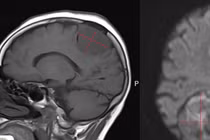

Chỉ đau đầu nhẹ, đi khám phát hiện u não lớn phức tạp

U màng não có thể xảy ra với bất kỳ ai, thường phát triển âm thầm, khi được phát hiện khối u đã có kích thước lớn, người bệnh đối mặt với nhiều biến chứng.